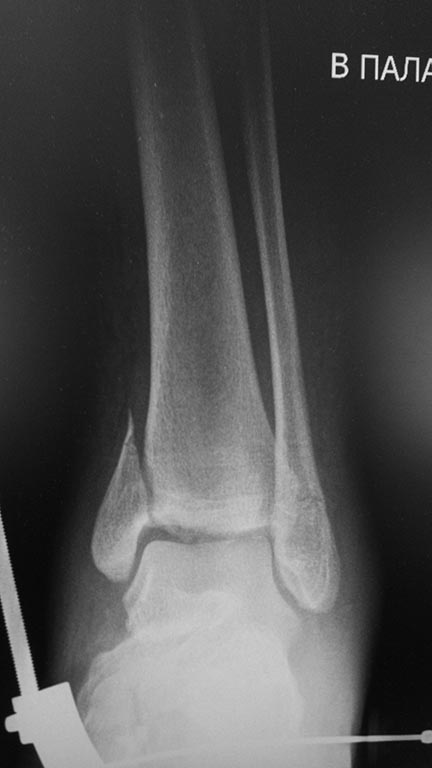

Мужчина, 1987 г.р. получил травму 10.2014. ДТП. Закрытый двухлодыжечный

перелом костей костей левой голени, перелом заднего края большеберцовой

кости с подвывихом стопы кзади, кнаружи. Наложен дистрактор.

На момент обращения: жалобы на боль в левом голеностопном суставе.

Работать не может (работает водителем). Без дополнительной опоры может

пройти до 20-30 метров. Отечности мягких тканей нет.

Какой план лечения,на Ваш взгляд, предпочтительнее в данном случае?

Возможно ли одномоментно устранить подвывих или только на аппарате

Иллизарова? Первичные снимки после травмы отсутствуют. Критично ли

"растоптана" латеральная суставная поверхность большеберцовой кости?